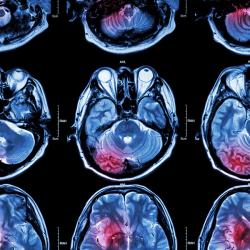

Following the results of a hypothesis-generating study of immunotherapy in glioblastoma, a type of brain cancer, a phase 2 clinical trial is set to evaluate Opdivo (nivolumab) with or without relatlimab, a combination known as Opdualag, among patients with isocitrate dehydrogenase (IDH)-wildtype newly diagnosed glioblastoma.

The Nature Medicine article looked at the case of one patient with IDH-wild-type, MGMT promoter unmethylated glioblastoma who received treatment with a single dose of triplet immunotherapy followed by surgery who, after 17 months, showed no definitive sign of recurrence.